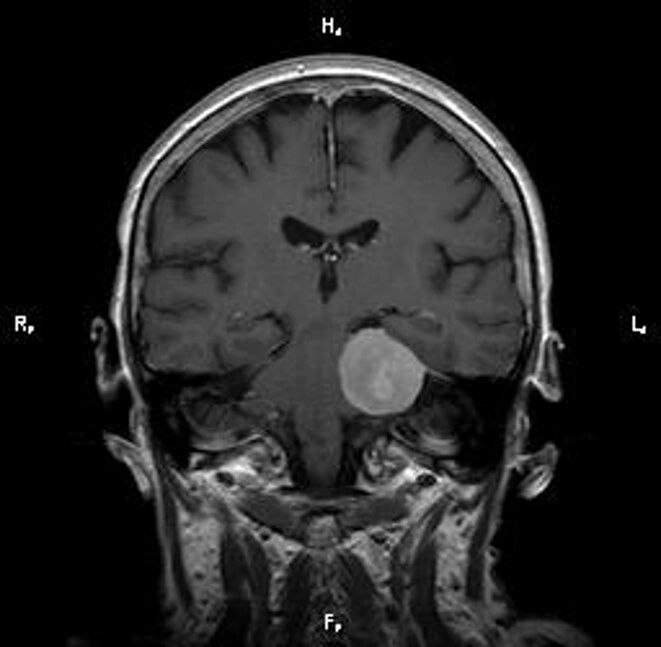

Опухоли после мрт

Опухоли после мрт 113 фото